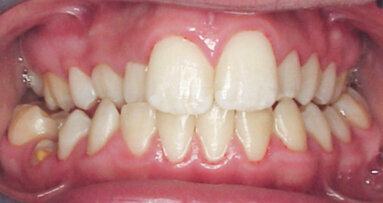

Komplexní klinická studie ukázala, že endodontické léčebné protokoly zahrnující nástroje Reciproc (Dentsply Sirona) podporují lepší léčebné...